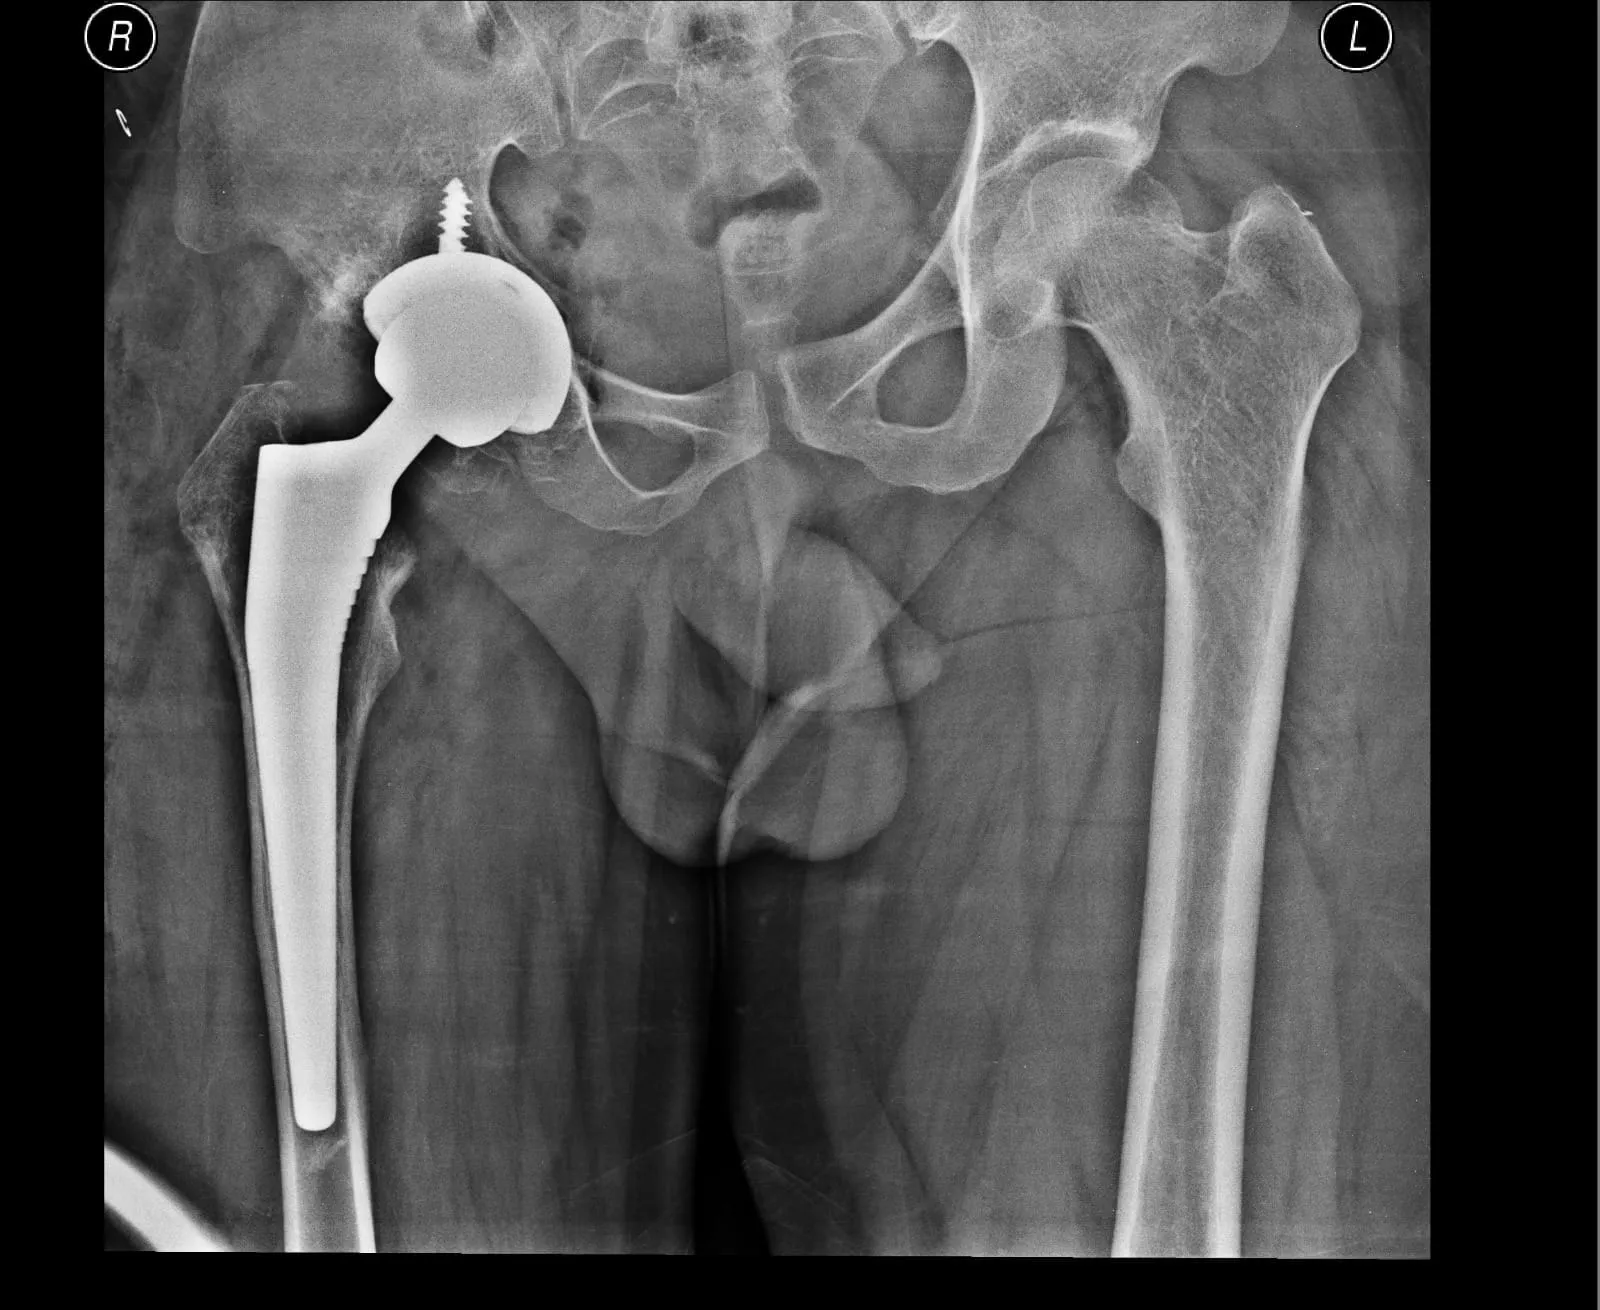

Quality and affordable healthcare has long been the essence in the field of medical sciences & treatment. Every patient expects an early diagnosis and a planned approach to treatment procedures with affordability and access to quality healthcare. Knee replacement, Hip replacement, Fracture treatment are being done by Dr.P.Sankaralingam at very affordable costs without compromising on quality.

Dr.P.Sankaralingam M.S(ortho)., DNB (ortho).,MNAMS is an experienced senior consultant Orthopaedic surgeon who does about 350 joint replacement surgeries per year in addition to treatment of Trauma cases.

Standard Hospital, Chennai’s Centre of Excellence for Orthopaedics offers minimally invasive surgeries for faster recovery.